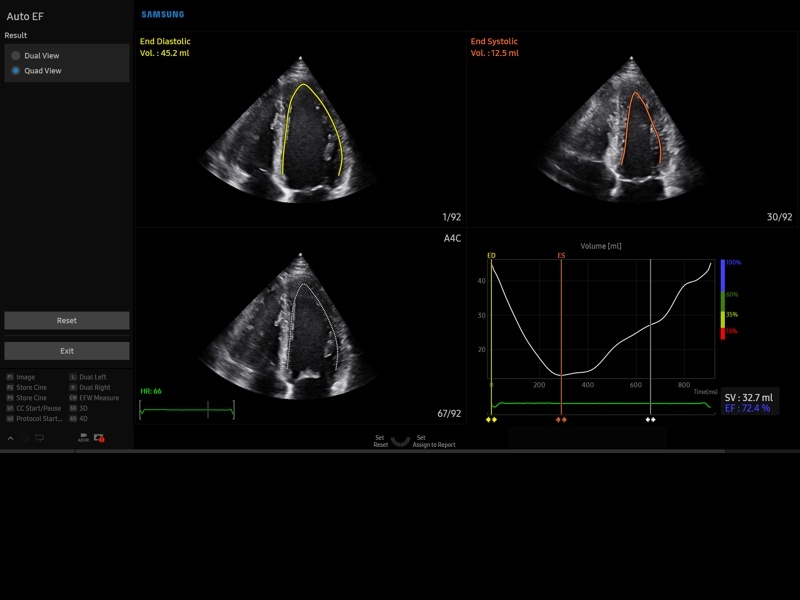

• Пакет кардиологических исследований.

М-режим:измерение диаметра аорты, передне-заднего размера ЛП, толщины МЖП (систолическая и диастолическая), толщины ЗСЛЖ (систолическая и диастолическая), размеров ЛЖ и ПЖ (систолический и диастолический), ФВ (Teichholz).

B-режим:измерение диаметра аорты (восходящей, дуги, нисходящей, на уровне синусов Вальсальвы, на уровне створок аортального клапана), определение размеров ЛП и ПП (максимальный, минимальный, систолический, диастолический, переднее-задний, верхнее-нижний, медиально-латеральный), расчет объемов ЛП и ПП, объемов ЛЖ (метод "Площадь-Длина", метод дисков (Simpson)), массы миокарда ЛЖ, индекса массы миокарда ЛЖ.

• МодульStrain+- программа не векторной оценки степени сократимости миокарда с выведением автоматически расчетов и графиков на экране отдельно по каждому сегменту.

• Модуль Stress Echo – программа для исследования сердца под нагрузкой.

• Кардиология